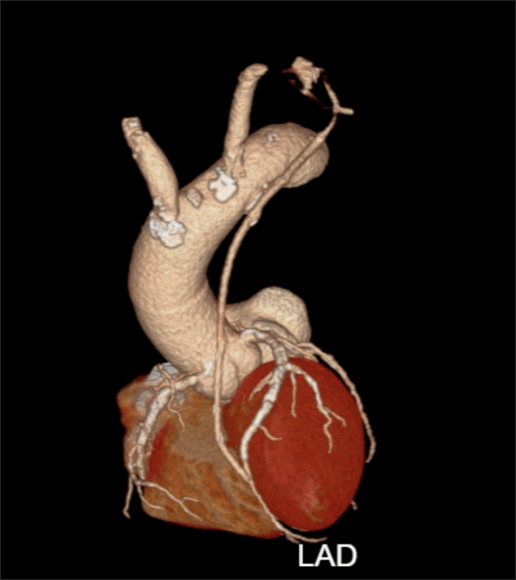

术后复查冠脉CT显示桥血管通畅